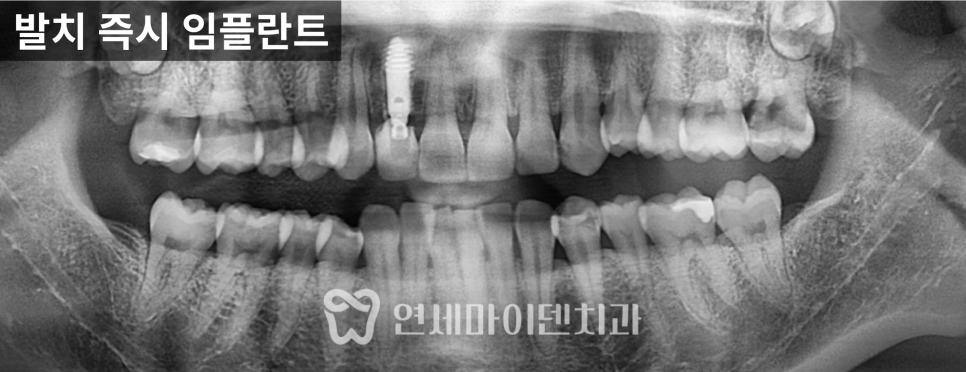

2차 치료: 반대편 회복

시간이 지나면서

반대편도 불편감이 증가해

추가 치료를 진행하게 되었습니다.

위쪽 2개, 아래쪽 2개

4개의 임플란트를 계획했습니다.

발치 후 내부를 확인하니

오랜 기간 축적된 세균막이 관찰되었습니다.

이러한 세균막은

치주질환을 악화시키는 원인이 되기 때문에

초기 정리가 매우 중요합니다.